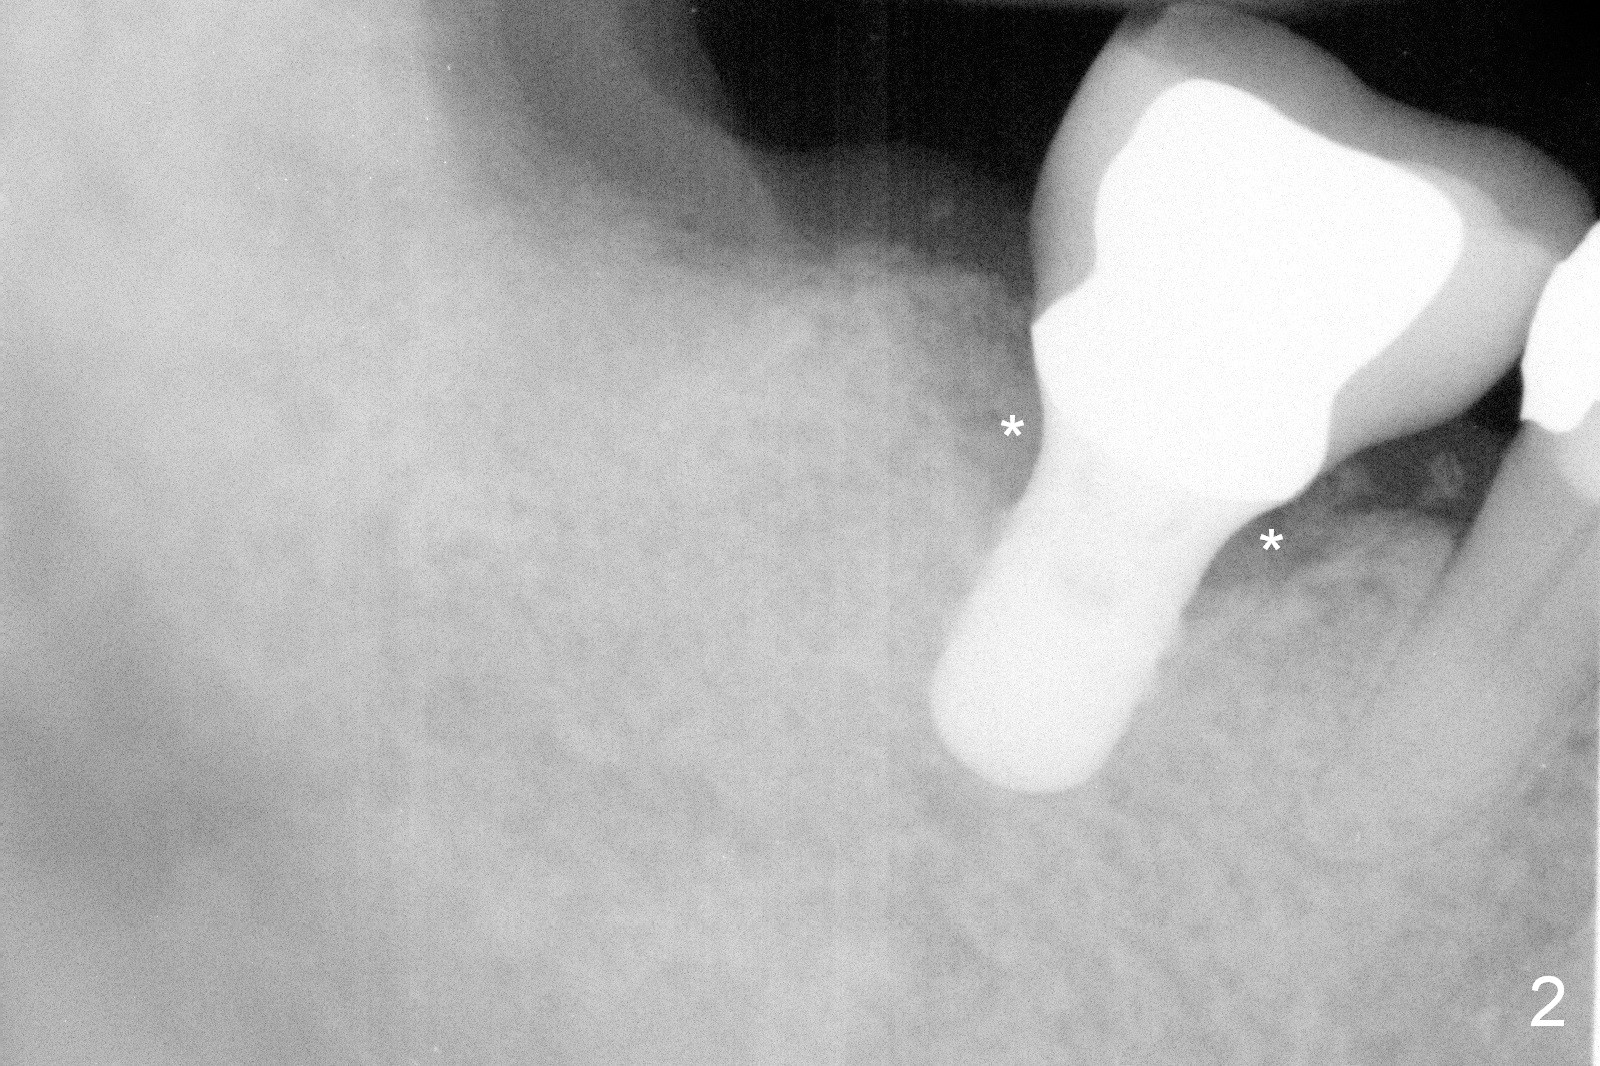

A 75-year-old man has apparent history of bruxism. The distal root of the tooth #31 had vertical fracture after root canal therapy. The tooth was extracted ~ 2 months ago while he returned to home country. It appears that there is buccal plate atrophy (Fig.1 S: socket).

Incision will be made to determine pattern of bone resorption and where to initiate osteotomy. Although the soft tissue of the socket (Fig.1 S) has healed, the bone must be still healing (soft, Fig.2 radiolucent socket). Use DIO starter drill, 2 mm pilot drill set at 12 mm (4 mm implant spacer) and short and marked parallel pins. Keep the last pin in place and take PA and photos. Change trajectory with Lindamann bur in the cassette if needed. Then start using bone expanders as large and deep as possible. The bone beyond the socket may be not as soft. Keep the largest expander in place and take photos. We want to confirm that not only is the buccal plate able to be expanded, but also the plate can be increased coronally to certain degree.